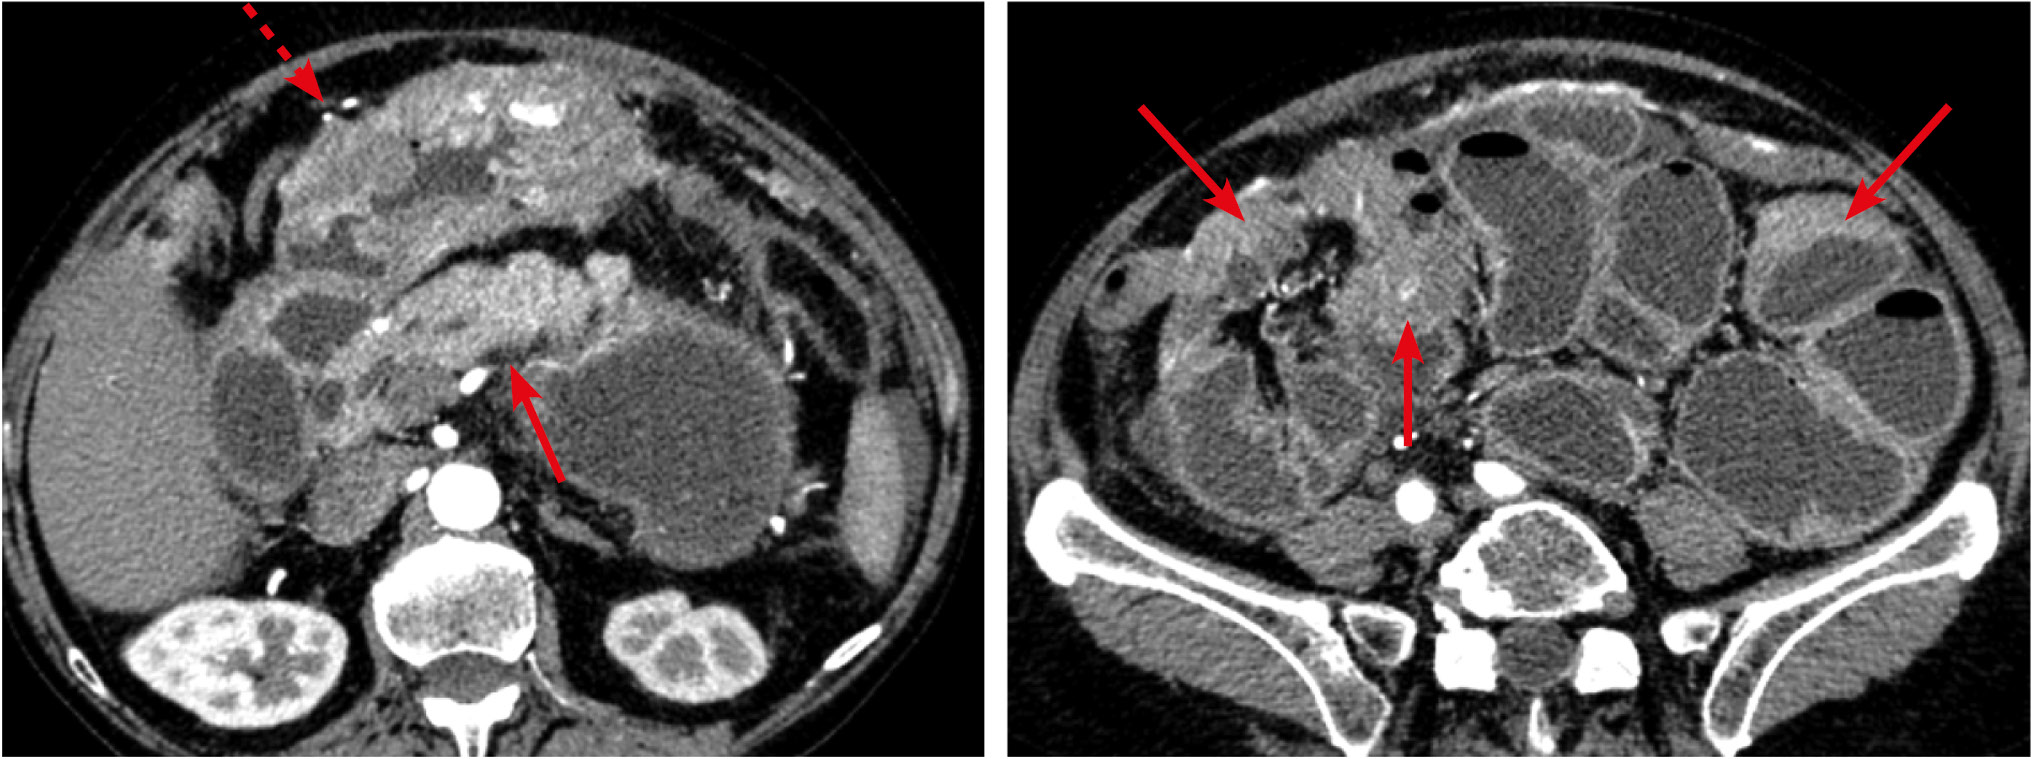

Рис. 7. Больная, 68 лет. МСКТ: первично-множественная синхронная лимфома (мезентериальная форма). Артериальная фаза контрастного усиления

Примечание. Определяются утолщения стенки желудка (стрелка), тонкой (обозначены овалом) и сигмовидной кишок. Четко визуализируется распространение лимфоидной инфильтрации на несколько рядом расположенных сегментов тощей кишки. Утолщение стенки кишки сопровождается умеренным и неравномерным расширением просвета. При контрастном усилении наблюдается повышенное контрастное усиление пораженных участков, в большей степени за счет слизистого слоя. Хорошо видны увеличенные лимфатические узлы в большом сальнике (пунктирная стрелка) и забрюшинном пространстве.

Метастатическое поражение висцеральных листков брюшины вызвало утолщение стенки кишки у 16 (18,6%) больных. Причинами вторичного поражения брюшины чаще служили опухоли желудочно-кишечного тракта и поджелудочной железы. На томограммах метастатическое поражение брюшины проявлялось отложением солидных масс в виде плоскостных или бугристых утолщений на покрывающих кишечник серозных оболочках (рис. 11). При прогрессировании определялась инвазия опухоли в стенку кишки с утолщением стенки и сужением просвета, что вызывало кишечную непроходимость. Поражение чаще носило множественный характер. По протяженности сегментарные утолщения (67%) встречались чаще фокальных (33%), с прогностическим значением положительного результата 20 и 12,2% соответственно. Распространенные поражения сопровождались скоплением жидкости в брюшной полости. При контрастном усилении солидные массы на серозных оболочках характеризовались повышенным контрастным усилением.

Рис. 11. Больная, 68 лет. МСКТ: рак желудка. Метастатическое поражение серозных оболочек. Кишечная непроходимость. Артериальная фаза контрастного усиления

Примечание. В антральном отделе желудка определяется опухоль (пунктирная стрелка). Визуализируются неравномерные утолщения стенки кишки, обусловленные вторичным поражением серозных покровов (стрелки).